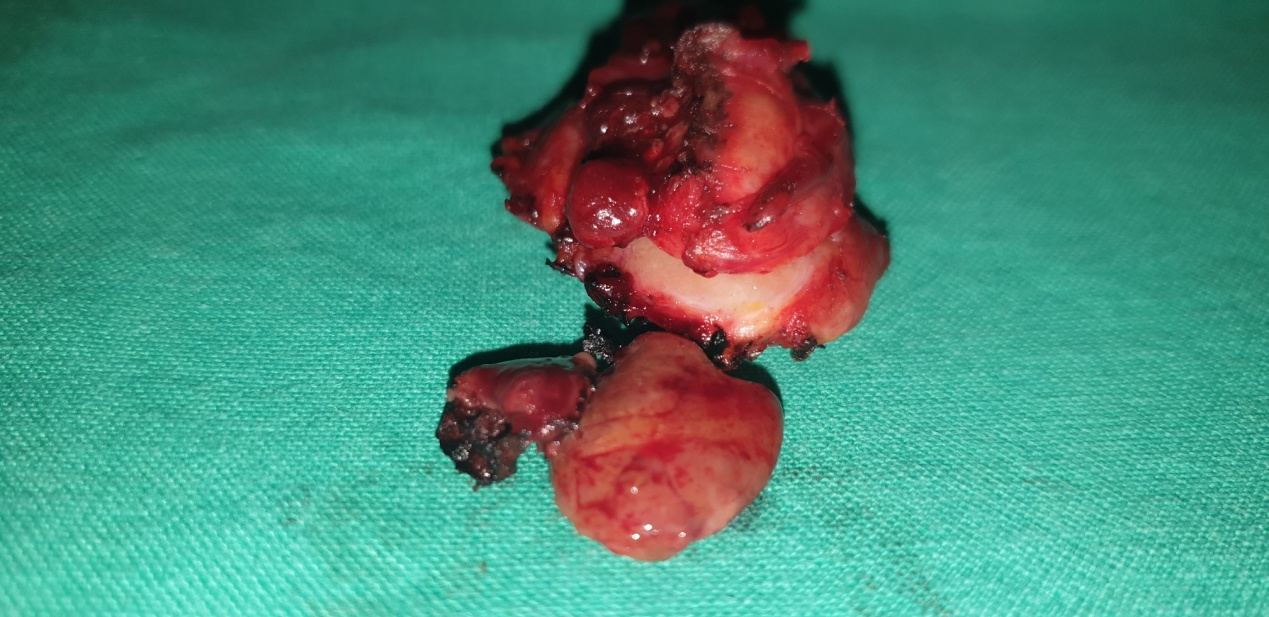

Figure 5 . Surgical specimen a) Blue arrows: encapsulated medullary microcarcinoma b) Yellow arrows : parathyroid glands . c) Green arrow : Benign thyroid nodule . ( Courtesy Dr . V . Penopoulos ) .